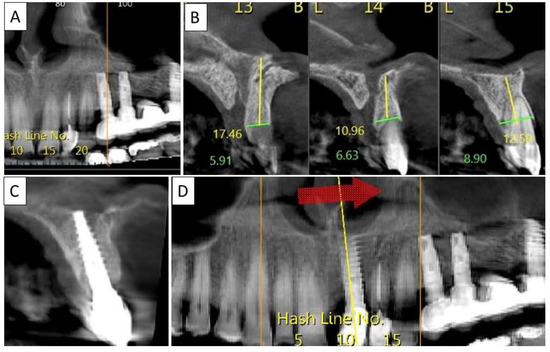

Four months post operatively, there was an excellent regeneration of bone defect including a fully regenerated cortical buccal plate (Figure 9). The implant was stable and there was a good healing of the soft tissues.

Figure 9.

(A) Panoramic CBCT section shows associated apical radiolucency of tooth 15. (B) Coronal CBCT section shows tooth 15 with vertical root fracture and destroyed buccal bony wall and intact palatine. (C) Panoramic CBCT section shows bone formation around the implant in area 15. The coronal CBCT section shows the implant placed in the region of tooth 15.